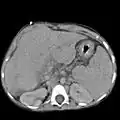

The hepatorenal recess[1] (subhepatic recess, pouch of Morison or Morison's pouch) is the subhepatic space that separates the liver from the right kidney. As a potential space, the recess is not normally filled with fluid. However, fluid can collect here in circumstances where the abdomen fills with fluid, such as hemoperitoneum. This fluid may be seen on ultrasound or computed tomography (CT scan).

Since it is a potential space, the hepatorenal recess is not normally filled with fluid. However, this space becomes significant in conditions in which fluid collects within the abdomen (most commonly ascites and hemoperitoneum). The intraperitoneal fluid, be it blood, ascites, or dialysate, collects in this space and may be visualized, most commonly via ultrasound or computed tomography (CT) scanning. As little as 30 or 40 ml of fluid in the abdominal cavity may be visualized in this space.

Early visualization of fluid in the hepatorenal recess on FAST scan may be an indication for urgent laparotomy.[2]